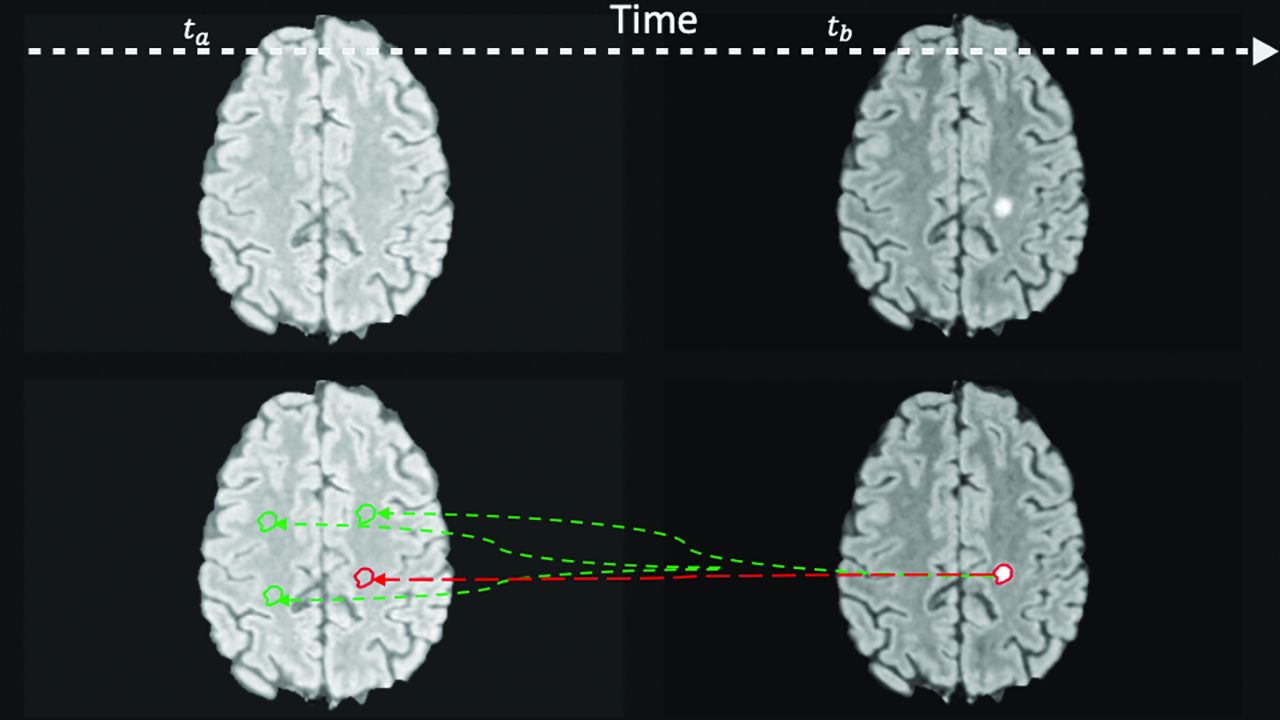

New lesion segmentations were projected backward in time to the same location (dubbed the prelesion) on the prior MR imaging study. This same segmentation was then randomly translated 3 times to other locations within the NAWM to produce 3 control segmentations (Fig 2). The NAWM mask was obtained by subtracting the lesion mask from the white matter mask generated by FSL. By means of PyRadiomics (Version 3.01; https://pypi.org/project/pyradiomics/),34 high-order image features were extracted from the prelesion and control segmentations (Fig 3). The 3 control features were averaged to gain a fairer representation of the NAWM. Because the shapes of the control segmentations were dependent on the original lesion segmentations, shape-related radiomic features were excluded.

Prelesion and control masks. Expert segmentation mask at time b (tb) is projected backward to time a (ta) to the location where a lesion will occur (prelesion, red) and the other random areas in the NAWM (control, green). Note that this 2D representation is for illustrative purposes only, and for the experiments, the random translation was in 3D.